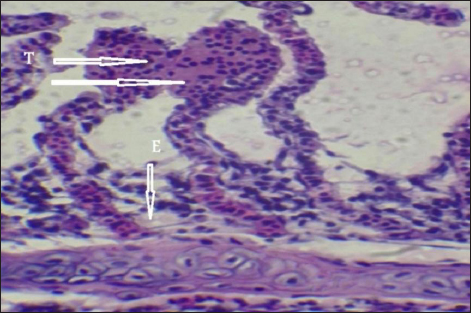

Histopathological findings of gill section showed telangictatisis and epithelial lifting in secondary lamellae (Fig. 7) with hemorrhage and blood congestion (Fig. 8), also, the result showed the central venous dilation with blood congestion and epithelium hyperplasia with complete fusion of the secondary lamellae (Figs. 9 and 10) and edema in the filamentary epithelium (Fig. 11) in addition to mononuclear cells infiltration (Figs. 12 and 13).

Fig. 7. Histopathological sections of gill of C. carpio showing telangictatisis (T) and epithelial lifting (EPL) (H&E X10).